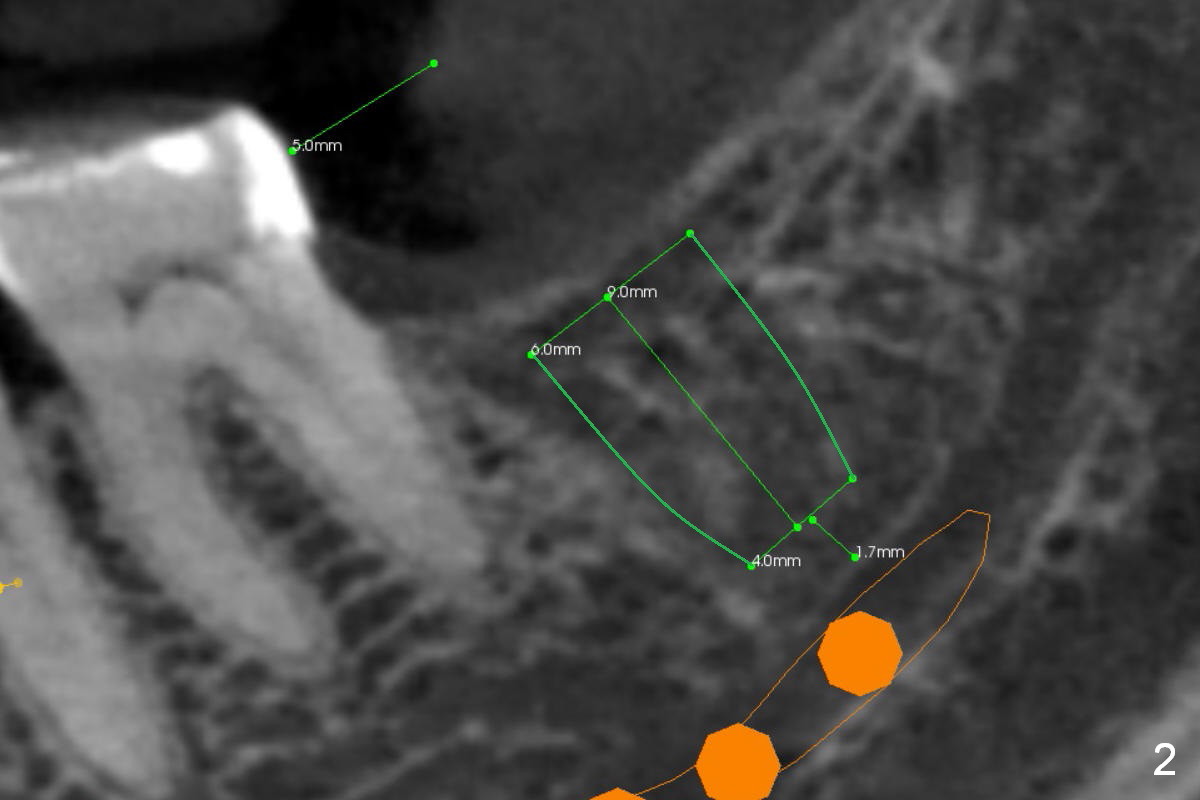

A 65-year-old woman is afraid of dentistry.  After loss of the tooth #18 (Fig.1 with upper RPD), she feels necessary to have an implant (Fig.2).  Since the ridge is wide (Fig.3), a flapless approach is adopted (Magic Split, measure the diameter of its handle).  After 1.6 mm pilot drill (9 mm stopper) and Marking Drill (know the diameter of the large portion), use 4.8 mm Magic Drill (spacer set 2.5 mm, stopper 11 mm).  Try in 5.5x9 mm dummy implant and most likely 6x9 mm definitive one.